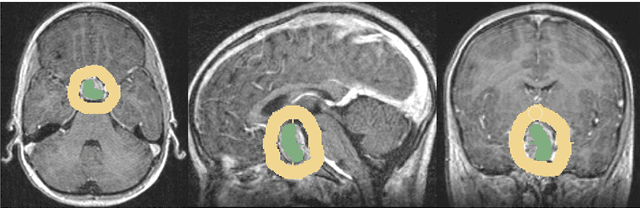

In this study, we present pituitary adenoma volumetry using the free and open source medical image computing platform for biomedical research: (3D) Slicer. Volumetric changes in cerebral pathologies like pituitary adenomas are a critical factor in treatment decisions by physicians and in general the volume is acquired manually. Therefore, manual slice-by-slice segmentations in magnetic resonance imaging (MRI) data, which have been obtained at regular intervals, are performed. In contrast to this manual time consuming slice-by-slice segmentation process Slicer is an alternative which can be significantly faster and less user intensive. In this contribution, we compare pure manual segmentations of ten pituitary adenomas with semi-automatic segmentations under Slicer. Thus, physicians drew the boundaries completely manually on a slice-by-slice basis and performed a Slicer-enhanced segmentation using the competitive region-growing based module of Slicer named GrowCut. Results showed that the time and user effort required for GrowCut-based segmentations were on average about thirty percent less than the pure manual segmentations. Furthermore, we calculated the Dice Similarity Coefficient (DSC) between the manual and the Slicer-based segmentations to proof that the two are comparable yielding an average DSC of 81.97\pm3.39%.